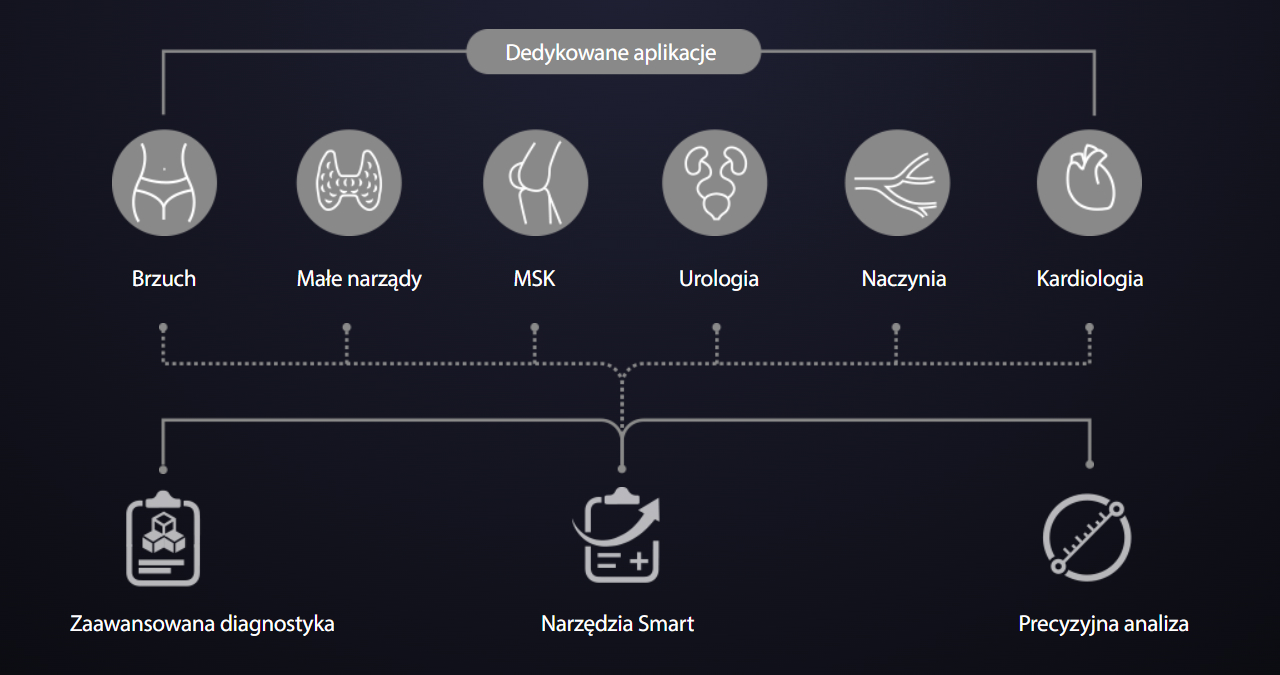

Zaawansowana diagnostyka